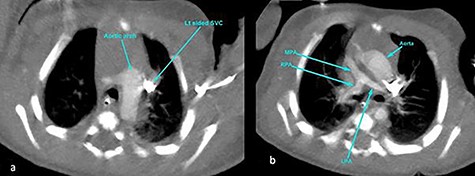

The subsequent pre-operative computed tomography angiography (CTA) thorax confirmed visceroatrial situs inversus, mirror image dextrocardia, tetralogy anatomy and left aortic arch with bovine branches. The MPA was hypoplastic (4 mm) with atretic origin. The right and left-sided pulmonary arteries measured 4 and 3 mm, respectively, as compared with the aorta (8 mm). A right PDA was seen originating from the brachiocephalic artery. The inferior part of the PDA was tortuous and connected to the proximal right pulmonary artery (Figs 2–4). At Day 20 of life, he underwent division of PDA, modified Blalock-Taussig shunt with Gore-Tex 3.5 mm between brachiocephalic artery (before bifurcation) and at the bifurcation of MPA through median sternotomy (Figs 5 and 6). The ascending aorta was twice the size of MPA, and the MPA was moderate in size (±3 mm). The right and left pulmonary arteries measured 4 and 3 mm, respectively. The tortuous and small PDA was noted to arise from the brachiocephalic artery, and it was connected to the proximal right pulmonary artery. Dissection of PDA has caused several episodes of hemodynamic instability, it was therefore decided to continue the procedure under normothermic cardiopulmonary bypass (CPB). It was easy weaning from cardiopulmonary bypass but with high doses of inotropes. In view of hemodynamic instability, the decision was made to leave the sternum open. He was transferred to the ICU in relatively labile condition, with high ventilator setting and inotropic support. He later developed pulmonary over circulation and remained intubated until Day 10 post surgery. He remained in the ICU and was discharged well on Day 26 post surgery. Serial post-operative echocardiography demonstrated good shunt flow with oxygen saturations maintained above 85% on air.

CT angiography thorax showing the left-sided aortic arch (a) and inverse relationship between ascending aorta and pulmonary artery. The MPA origin is atretic with hypoplastic RPA and LPA compared with the aorta (b). SVC, superior vena cava; RPA, right pulmonary artery; LPA, left pulmonary artery.